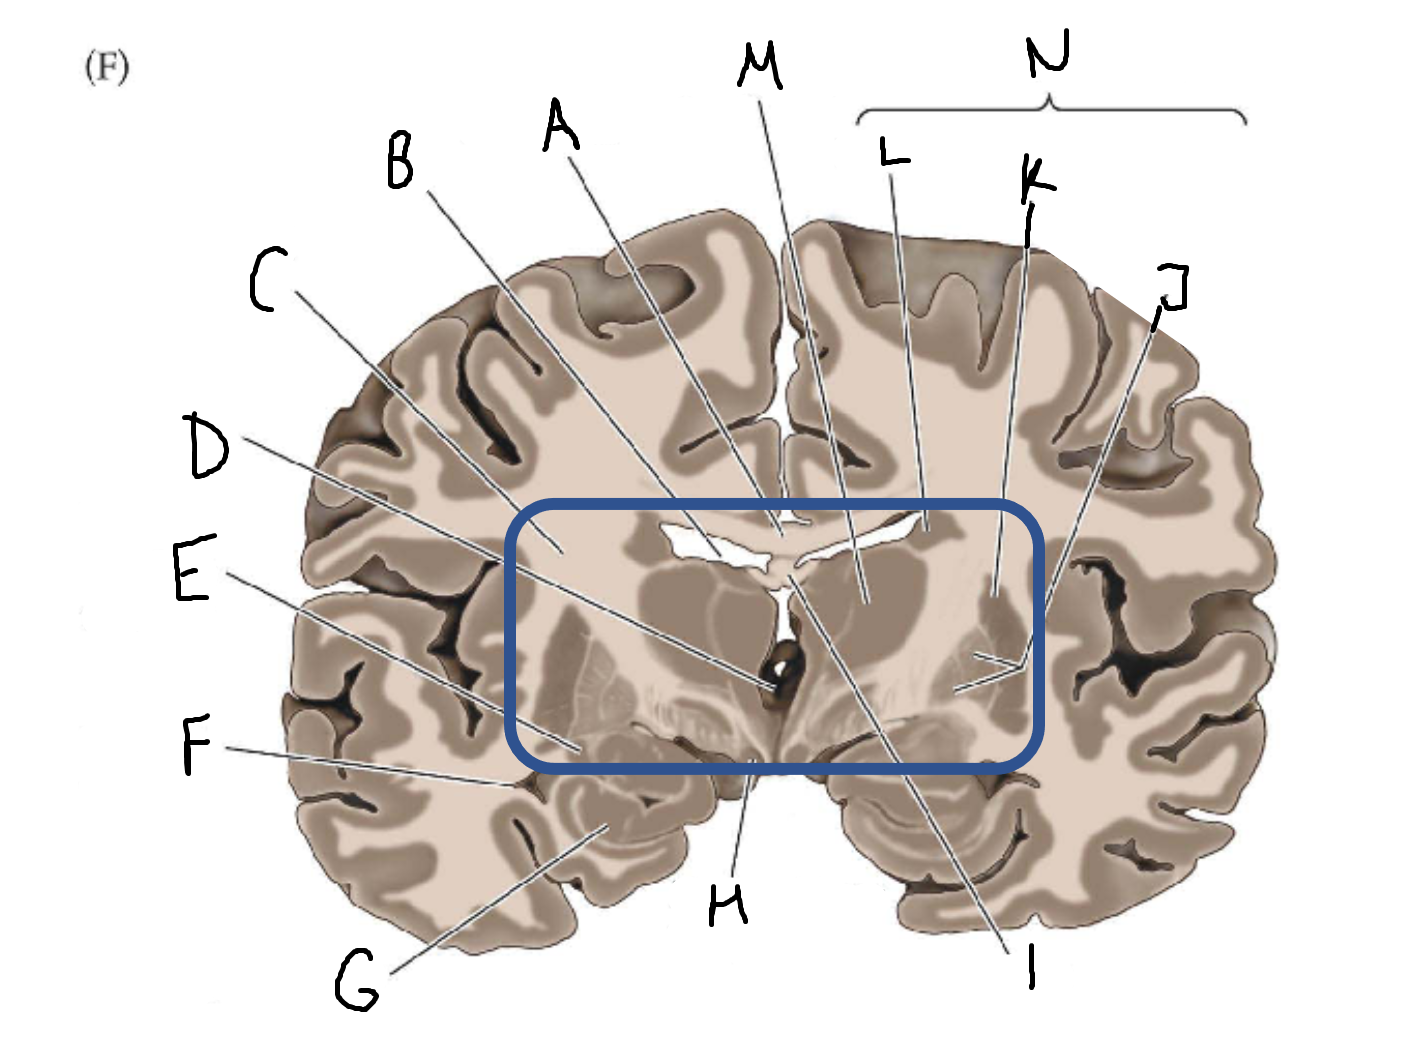

A

corpus callosum

B

lateral ventricle

C

internal capsule

D

third ventricle

E

tail of caudate nucleus

F

lateral ventricle

G

hippocampus

H

mammillary body

I

fornix

J

globus pallidus

K

putamen

L

caudate

M

thalamus

N

basal ganglia